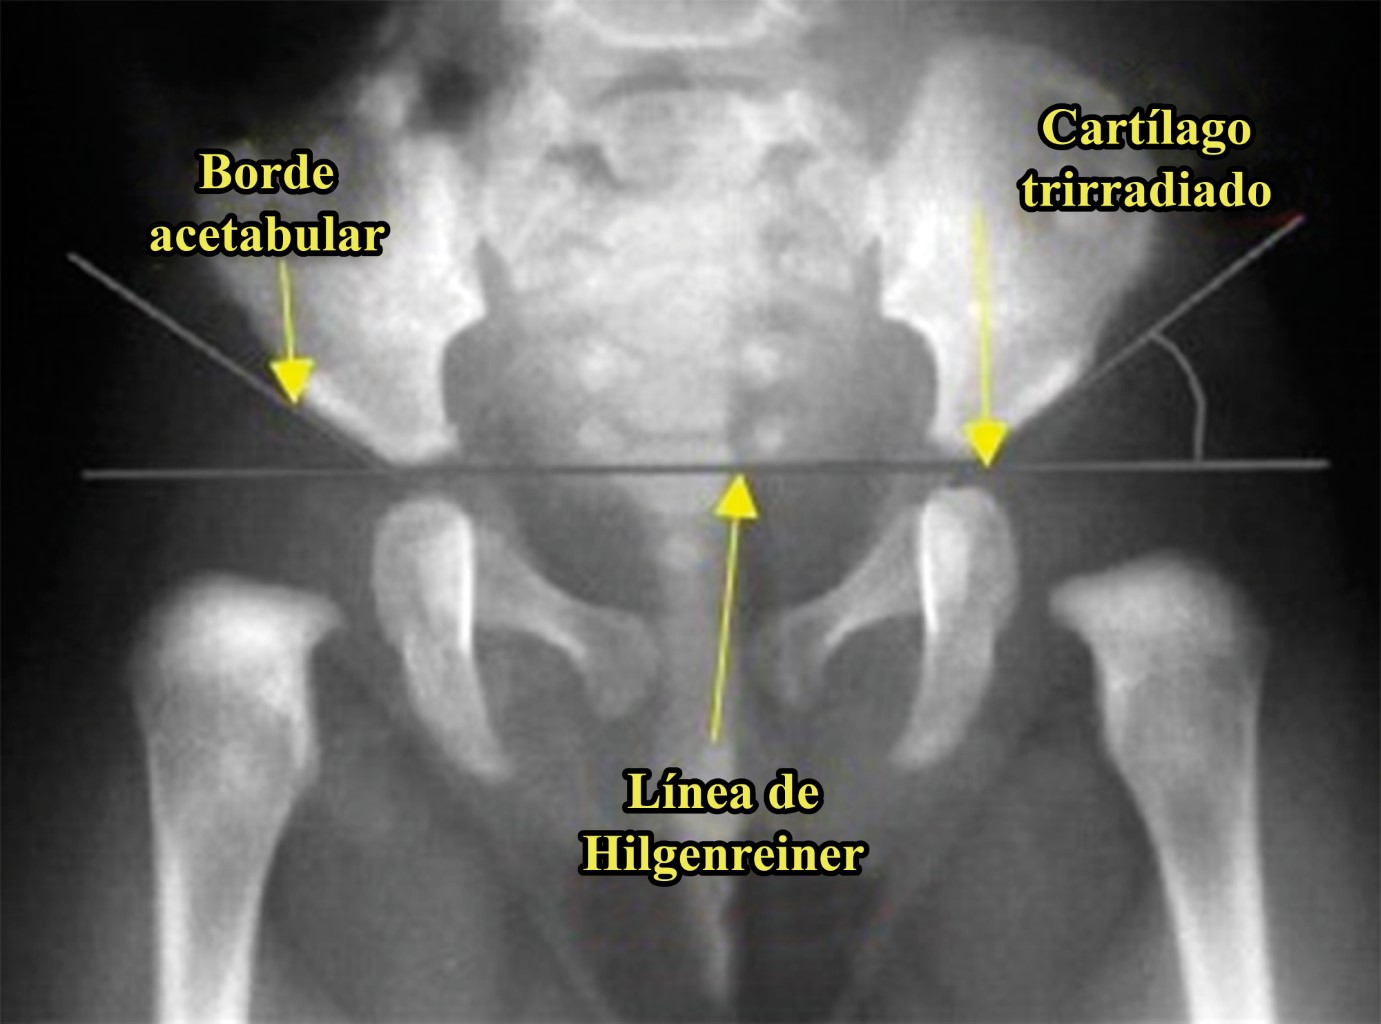

Application of the Graf method for diagnosis and early detection of hip dysplasia

Introduction: Developmental hip dysplasia (DHD) is the most common disorder affecting pediatric hip; screening all neonates clinically, and using ultrasonography selectively for those babies who are at high risk is a widespread recommendation. our goal is to evaluate the impact that USG diagnosis and early treatment of DHD has had on the child population of our unit. Material and methods: Retrospective, descriptive and cross-sectional study. Records of those children from one to six months of age, with a diagnosis of DHD, without distinction of sex, subjected to ultrasonographic tracking in the period from January 2018 to December 2019 were reviewed. A follow-up of six months was carried out in all patients, from the moment of diagnosis and the start of treatment with harness, weekly visits for relocation, as well as ultrasonographic revision every four weeks to monitor the treatment. Results: 19 cases were reported from the left side (47.5%), 10 cases from the right side (25%) and 11 bilateral cases (27.5%). The main associated risk factors were: product of the first pregnancy, family history of DHD, pelvic presentation, female sex. The results were favorable with a continuous use of harness of 23 hours observing a satisfactory evolution in 99.2% of the patients. Conclusion: With the results obtained we can analyze the considerable success rate of the hip clinic of our hospital with the realization of the ultrasound, we find a lower incidence of patients with pain, limitation of function, as well as satisfactory gait patterns.

Figure 3

Figure 4